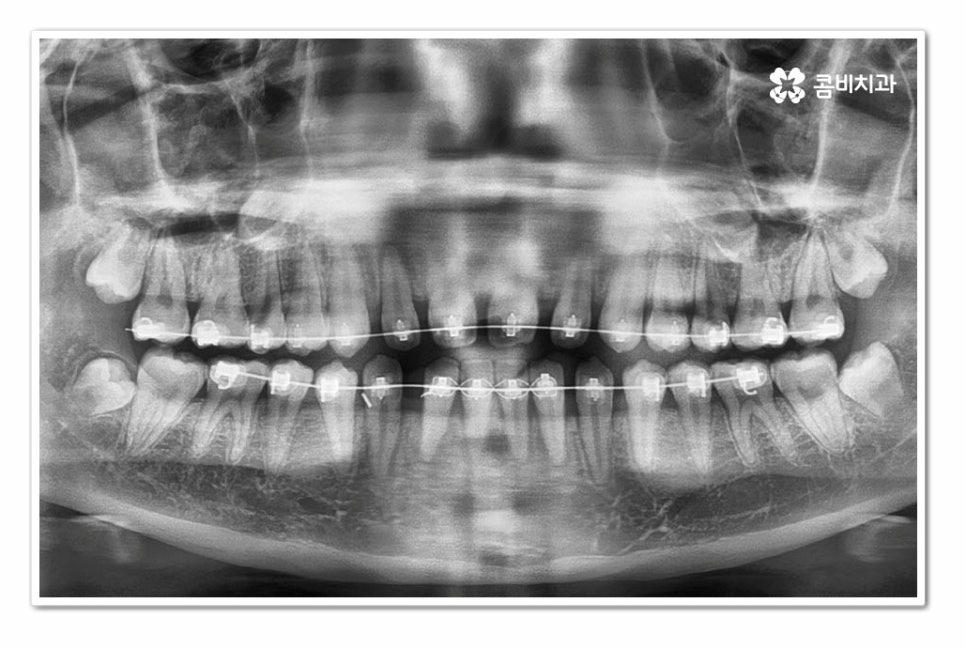

위 환자분의 경우 치아교정을 통해서 앞니 벌어짐 치료를 진행한 사례이며

치아의 이동 공간과 교합을 고려할 때 전체교정이 필요했던 사례라고 할 수 있어요.

오늘 보여드린 환자분의 케이스는 윗니와 아랫니가 모두 벌어져 있기 때문에

전체교정을 통해서 치료가 진행되었지만